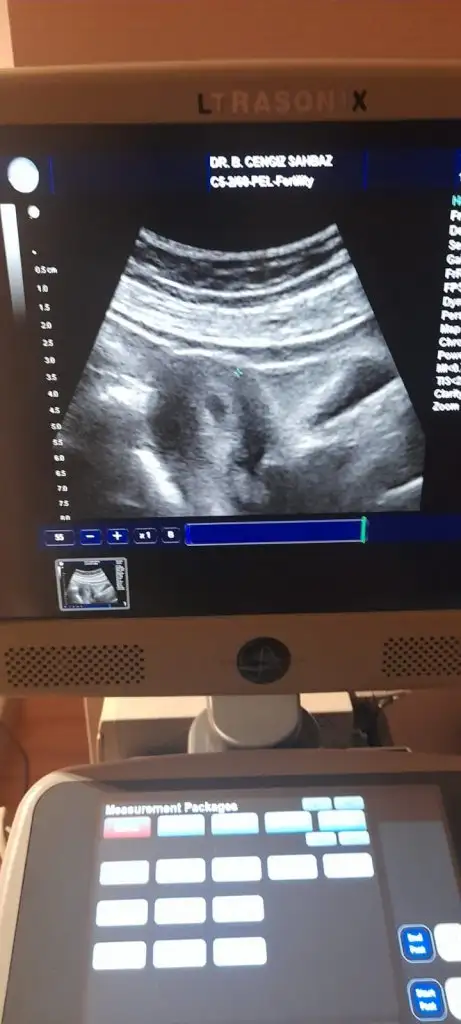

Kızlar Günaydın, bugün 5+1deyim pazar günü haftaici işten izin alamadığım için hiç tanımadığım saçma sapan bir doktora gitmek zorunda kaldım. 4+6 iken karından baktı ama beni hiç bilgilendirmedi gördüğüm şey kese mi 4+6da karından kese görünür mü hiç emin değilim doktor da yabancıydi hiçbir şey anlayamadım...

Görünür canım dün 4+5 dim göründü kese.